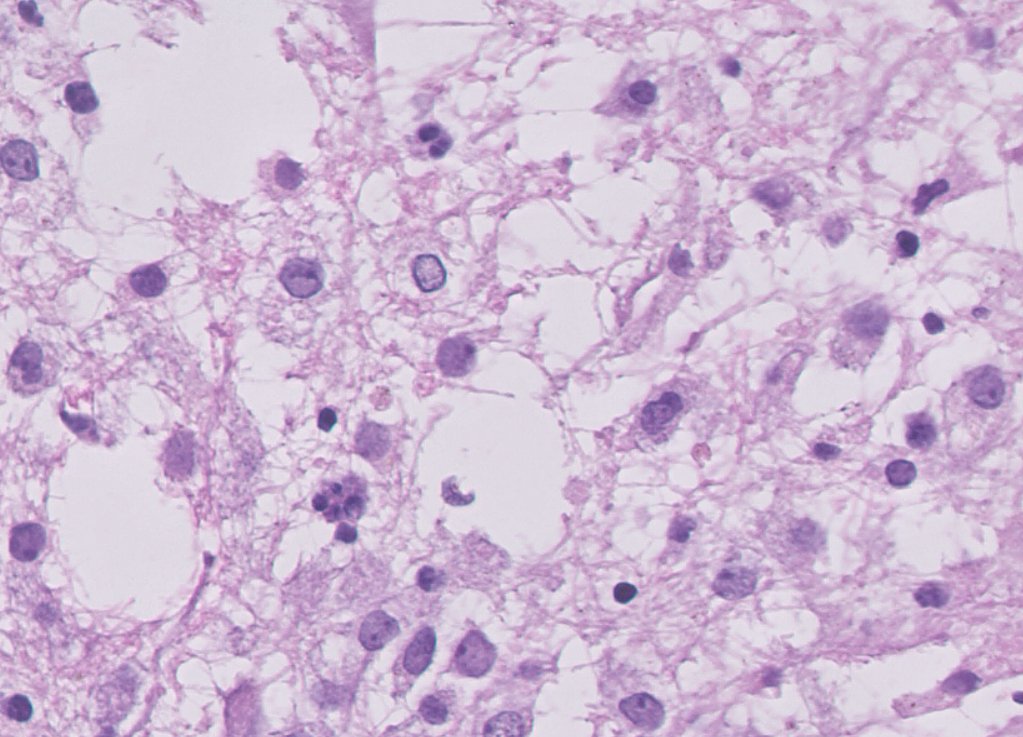

Call for #neuropath help: 60M Temporal lobe, cystic lesion, No necrosis, no mitoses, no MVP. IDH R132H neg, CD34+, EMAn neg, GFAP/Olig2 positive BRAF V600E neg. ?PLENTY ?Papillary glioneuronal tumour #pathtwitter #pathx #pathology